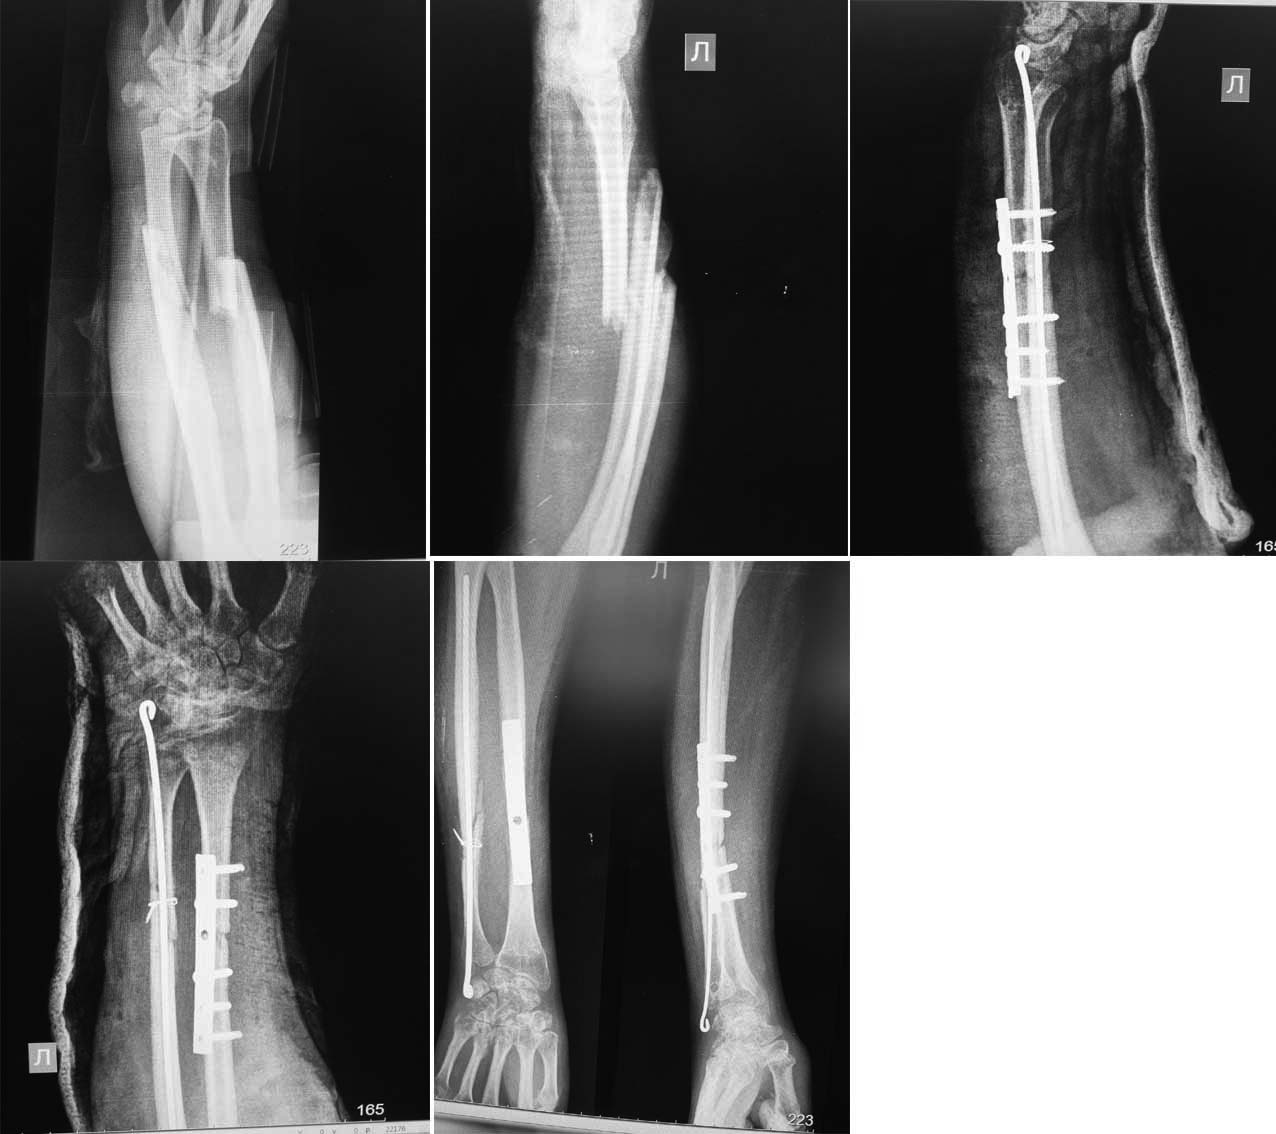

Добрый день, уважаемые коллеги!Женщина 34 года поступила с открытым переломом костей левого предплечья в июне 2014 года . Конечность попала под прокатный станок. При поступлении наложен АНФ, ПХО. В дальнейшем, произведена свободная кожная пластика раны тыла предплечья. 14 августа произведён демонтаж АНФ, остеосинтез перелома левой лучевой кости пластиной, винтами, остеосинтез перелома левой локтевой кости стержнем Богданова (поставить пластину не позволили мягкие ткани. Дистальный конец стержня слишком выступает из локтевой кости - погрешность операции. Претензии принимаются.)В послеоперационном периоде наложена гипсовая лонгета, которую сняли(то ли в поликлинике, то ли сама больная). Через месяц после операции появилась деформация предплечья. На контрольных снимках 16 октября - угловая деформация лучевой кости 15 градусов с деформацией пластины. Движения в локтевом суставе: сгибание, разгибание в полном объеме, ротация отсутствует. Наш план: ЛФК, разработка ротационных движений в локтевом суставе одна-две недели, затем попытка устранения деформации закрыто "на пластине". Иммобилизация. При неудаче, реостеосинтез. Возможно, сразу реостеосинтез.Какова тактика лечения предпочтительнее на Ваш взгляд?Заранее благодарен!

Пластина треть трубчатая, 5 кортикальных винтов. Недостаточно винтов, хотя бы еще один. Но главное: очень хилая пластина для данного случая. Штифт понятно, но зачем серкляж? Он что то дает к стабильности?

Если вести функционально, то реостеосинтез хотя бы 8 дырочной пластиной с ограниченным контактом по три винта с каждой стороны. Исправить ось и в гипс худший вариант. Хотя лет 20 назад вполне бы подошел. Если нет преемственности между стационаром и поликлиникой, или контакта с больной, надо делать с гарантией.

Остеосинтез изначально с погрешностями. Нужна абсолютная стабильность, которую ни гвоздь, ни пластина с 5 винтами не обеспечили. На мой взгляд - реостеосинтез двумя пластинами. Не исключена костная пластика на лучевой (смотреть интраоперационно). Ранняя разработка движений в локтевом и лучезапястном суставах. При накостном остеосинтезе по 3-4 винта в каждый отломок. Я бы взял узкие прямые пластинки на 8-9 отверстий. Удаление не ранее чем через 2 года.

Серкляж держит свободный отломок локтевой кости, а в пластине два кортикальных и три винта LCP. Более мощную пластину не позволили поставить мягкие ткани, если будем делать реостеосинтез, то возьмём более крепкую пластину.

В приложении немного похожий случай (6 месяцев после операции). Правда, пластины успели сломаться и сформировались ложные суставы. В нашем случае нагрузку разрешили сразу (после снятия швов и спадения отека пациент пересел за руль авто). Еще через 2 недели пациент вышел на работу.